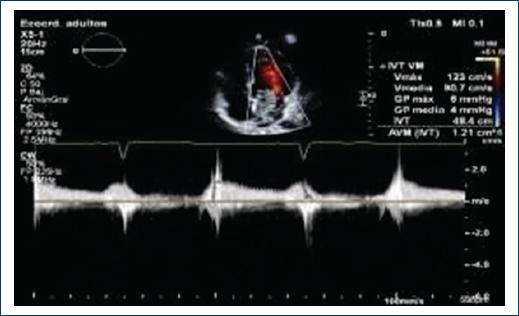

Transthoracic echocardiogram is observed in the left atrium with diameters of 37 × 37 × 49 mm, left atrium volume 38 mL/m2, multilobed and hypomobile tumor with the consistency of different echogenicities and cystic areas, of gelatinous consistency, adhered to the interatrial septum with a base of 25 × 27 mm very proximal at the anterior level of the septum and through it near the aortic valve. The size of the tumor is 40 × 20 mm and the larger lobe is 21 × 20 mm (Fig. 2), slides through the anterior leaflet of the mitral without being attached to it and interferes with the opening, causing functional stenosis of mild degree area by 3D planimetry 2.3 cm2, mean gradient 4 mm Hg, maximum velocity of 1.2 m/s, the insufficiency is mild with a 2 mm contract vein (Fig. 3).

Figure 3 Continuous Doppler to the mitral valve presents functional stenosis of mild grade medium gradient 4 mmHG Maximum velocity of 1.2 m/s, insufficiency is mild with contracta vein of 2 mm.